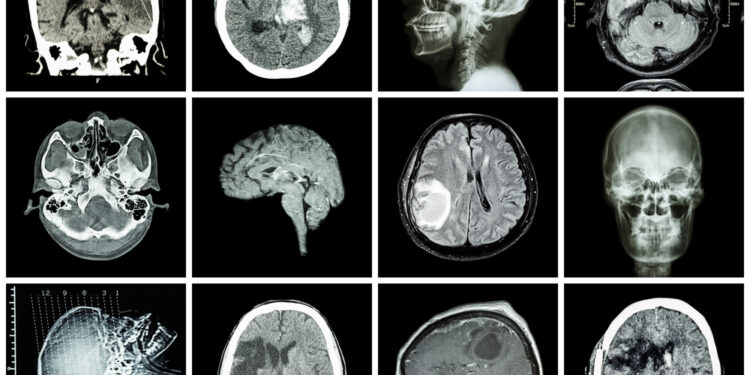

Pagrindiniai bazalinių ganglijų ištyrimo būdai

- Kompiuterinė tomografija (KT)

- Magnetinio rezonanso tomografija (MRT)